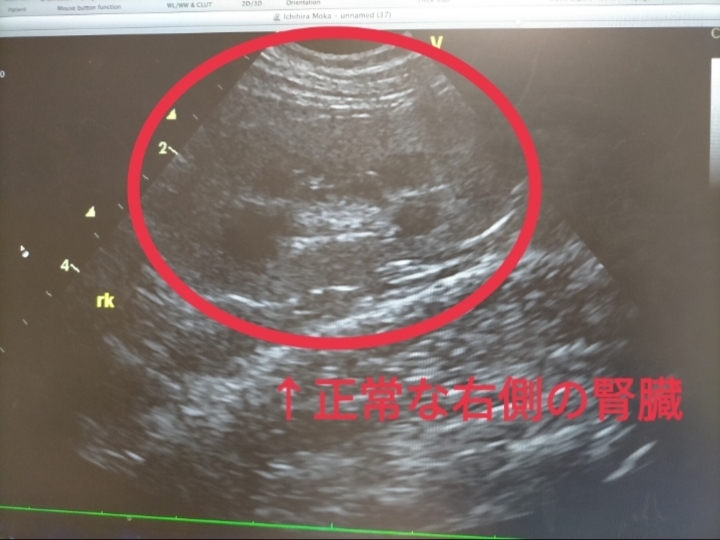

2024年11月5日🏥

いつものように検査をしていたら、

左側の腎臓だけ形がボコボコに…💦

今はステロイド治療ですっかり綺麗な形に戻り、その後薬を減らしてもずっと維持できているので、一過性の炎症の可能性もあるのですが…

実は発見当初、リンパ腫再発(転移疑い)の可能性が非常に高く、気が気ではありませんでした😭